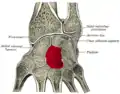

_01_palmar_view.png.webp) Left hand anterior view (palmar view). Capitate-bone shown in red. | |